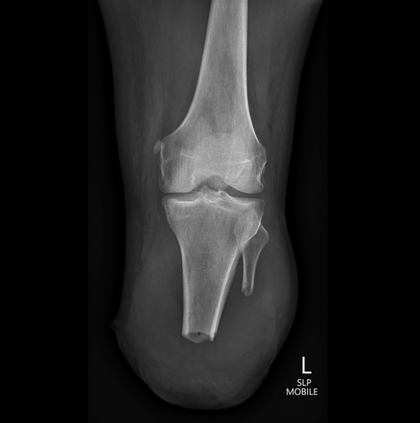

In this study, we aim to initiate the development of Radiology Foundation Model, termed as RadFM.We consider the construction of foundational models from the perspectives of data, model design, and evaluation thoroughly. Our contribution can be concluded as follows: (i), we construct a large-scale Medical Multi-modal Dataset, MedMD, consisting of 16M 2D and 3D medical scans. To the best of our knowledge, this is the first multi-modal dataset containing 3D medical scans. (ii), We propose an architecture that enables visually conditioned generative pre-training, allowing for the integration of text input interleaved with 2D or 3D medical scans to generate response for diverse radiologic tasks. The model was initially pre-trained on MedMD and subsequently domain-specific fine-tuned on RadMD, a radiologic cleaned version of MedMD, containing 3M radiologic visual-language pairs. (iii), we propose a new evaluation benchmark that comprises five tasks, aiming to comprehensively assess the capability of foundation models in handling practical clinical problems. Our experimental results confirm that RadFM significantly outperforms existing multi-modal foundation models. The codes, data, and model checkpoint will all be made publicly available to promote further research and development in the field.